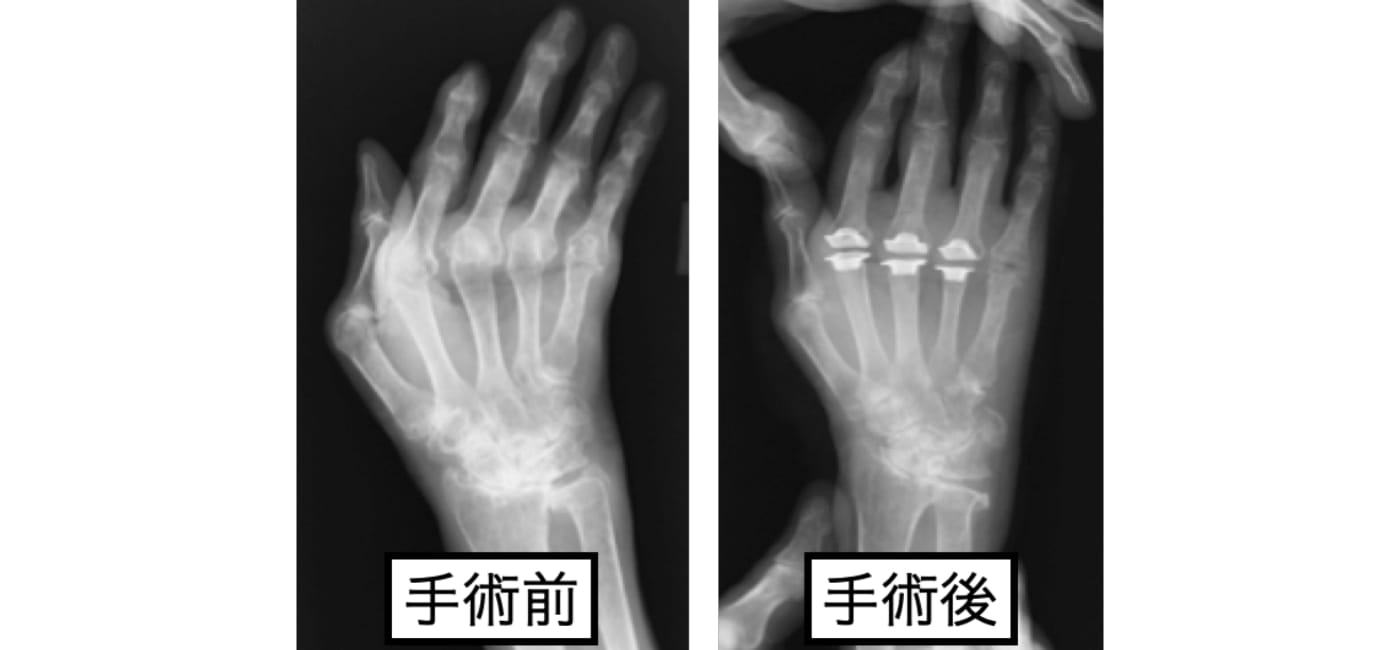

リウマチによる手部変形

リウマチによるMP関節の脱臼、尺側偏位を、シリコン人工関節を用いて手術を行った例です。

機能も大切ですが、手は一目にも触れるところです。人前に変形を気にせず、手を出せるようになりました。